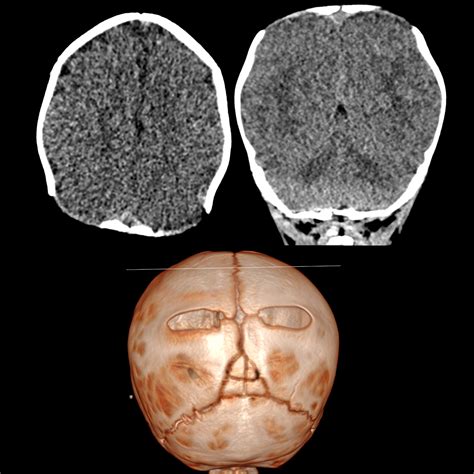

What Is Foraminal Narrowing Mean at Milla East blog